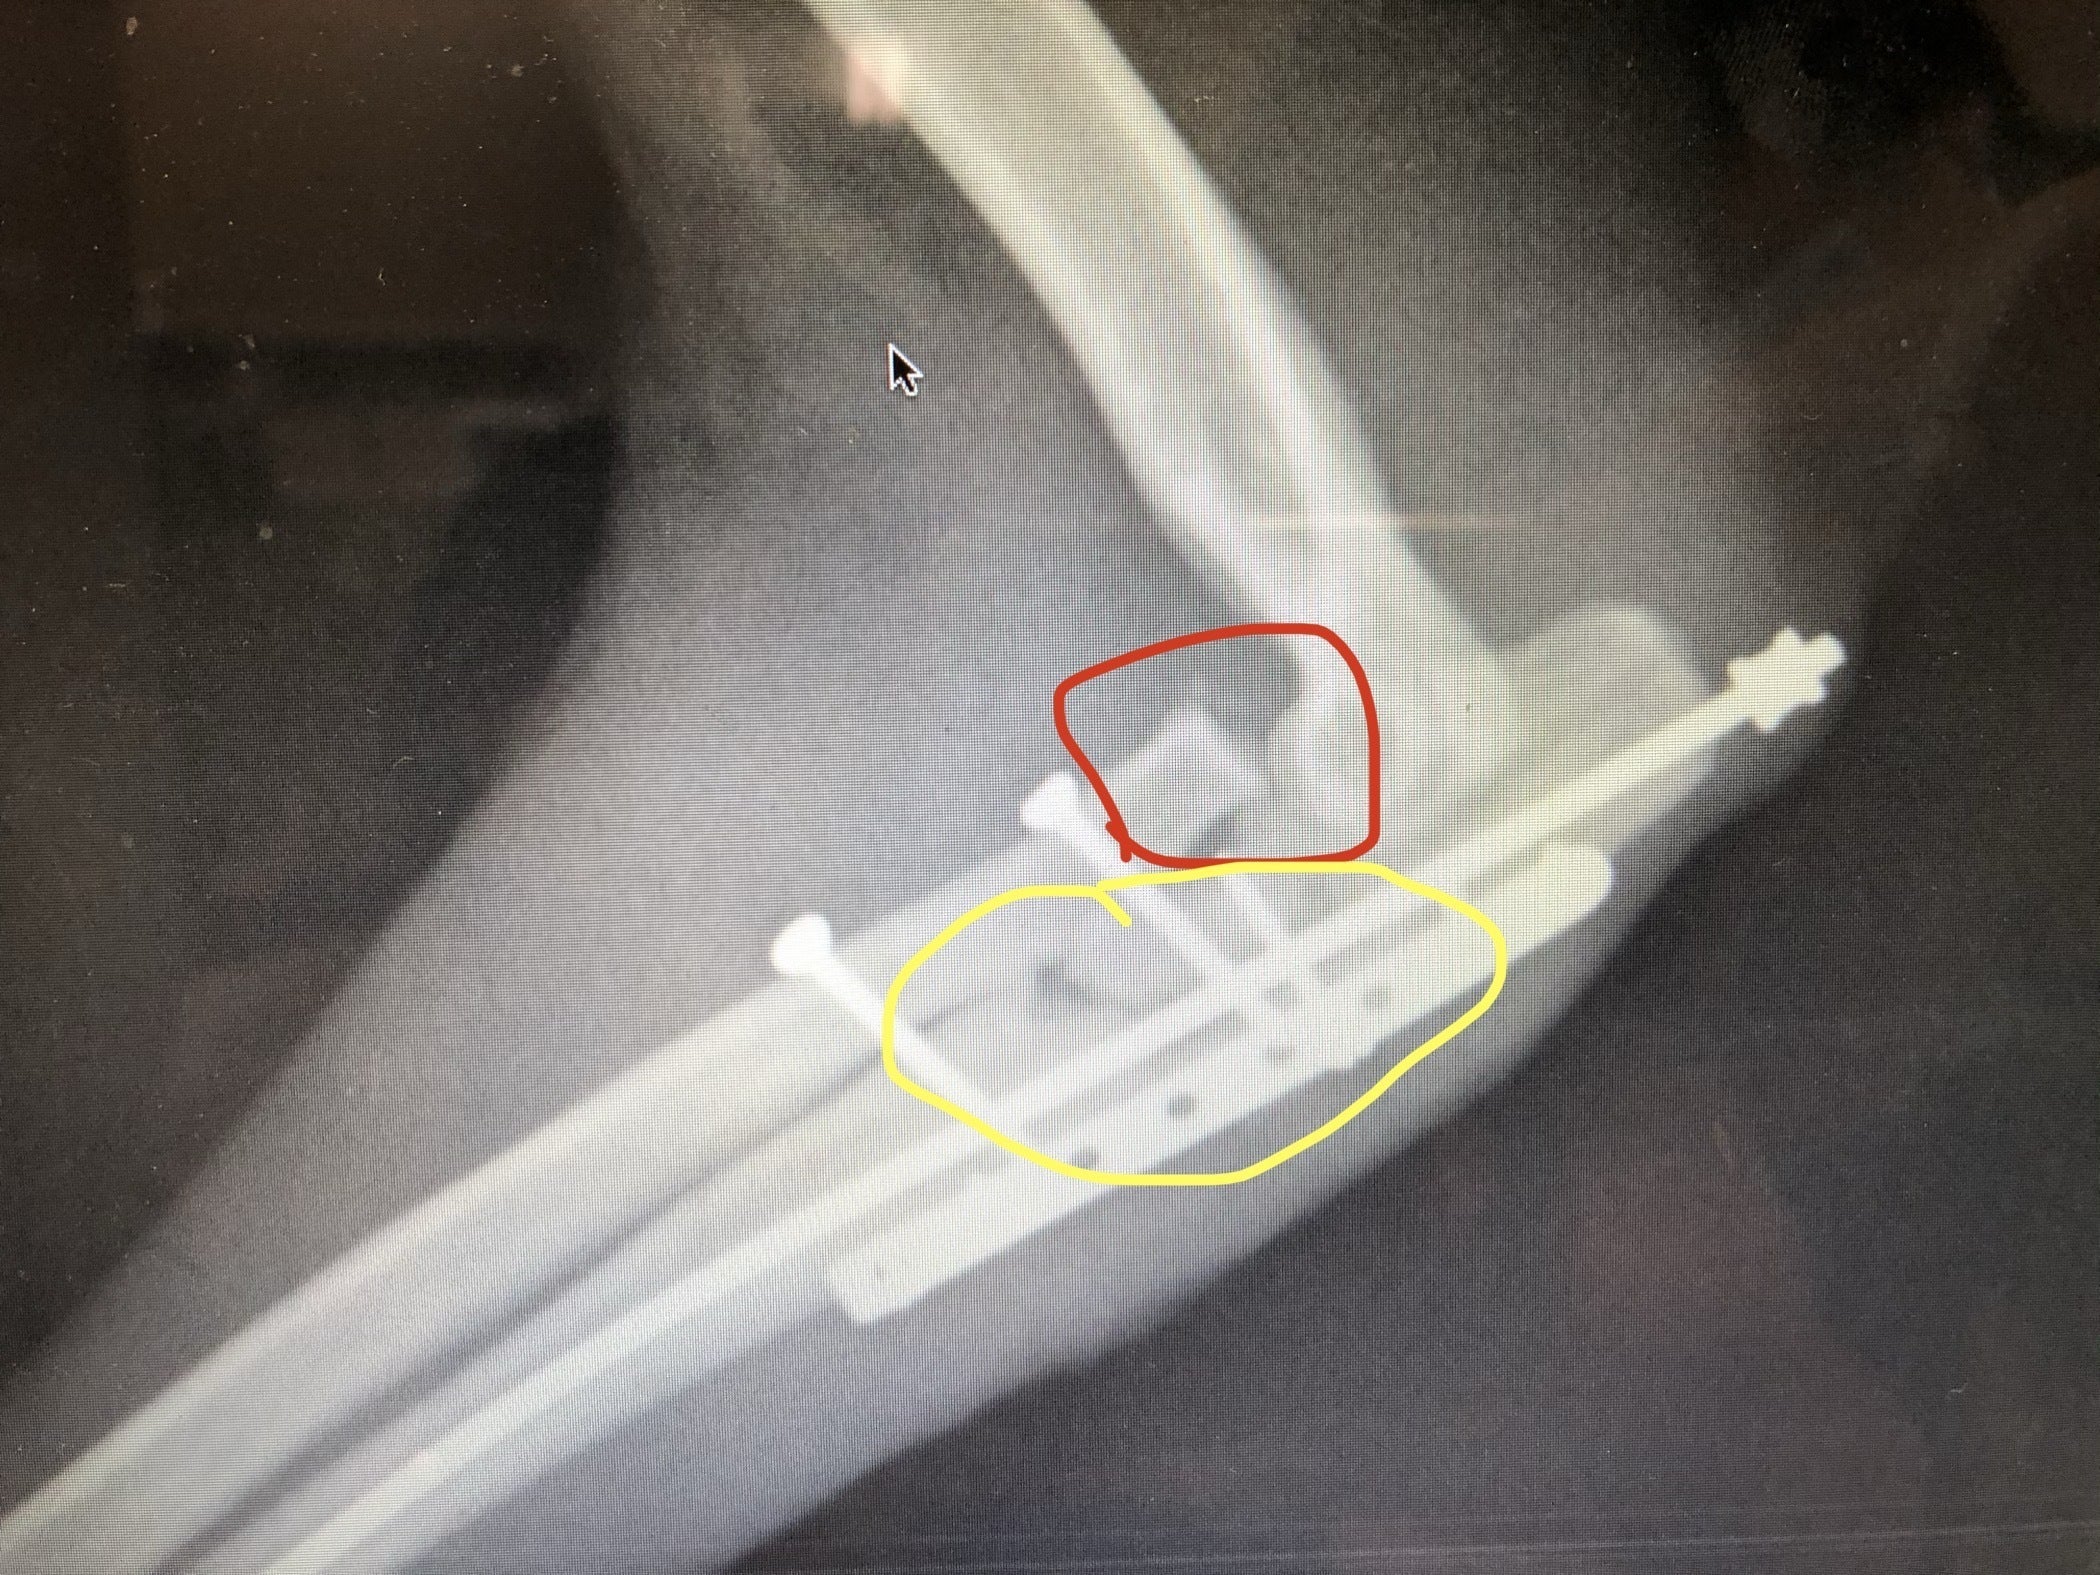

病院に連れていき、右前肢の「モンテジア骨折」、橈骨(とうこつ)の脱臼を伴う尺骨骨折という複雑な状態と診断されました。

チョリの右前肢について、当初医師から「このままでも命に別状はない。だが、一生の障害を負うことになる。手術をすれば、多少の後遺症(少し歩き方がぎこちない等)や関節炎のリスクはあるが、ちゃんと歩けるようになる」と聞かされ、私は「救える手があるのにしないのは一生後悔する」と感じ、手術をお願いしました。

骨の整復手術が行われ、その際に尺骨が粉砕骨折しているのがわかり、後の説明で「自分で遊んでるだけでは、粉砕骨折まではならない」と…。このプロジェクト開始時点では手術は無事終了していますが、まだこの先一か月後と二か月後の2回にわけて、整復手術で体内に入れたスクリュー、ピン、プレートの除去手術が残っています。

整復手術と入院・治療で50万円の費用が発生し、今後の2回の除去手術で約20万の見込みとなっています。

○レントゲン写真(赤○は脱臼箇所、黄色○は複雑骨折と骨折箇所)

同年08月03日 チョリの「モンテジア骨折」の整復手術実施、無事終了。ここから1週間入院となる。

チョリ退院予定も直前検査で固定のピンが抜けかけていることが判明、再手術要。

同年08月10日 チョリの再手術実施。右前肢前方から追加のスクリューを取り付け。無事終了。

同年09月06日 チョリの整復手術で取り付けた「スクリュー」「ピン」の除去手術実施予定。

同年10月08日 チョリの整復手術で取り付けた「プレート」の除去手術実施予定。